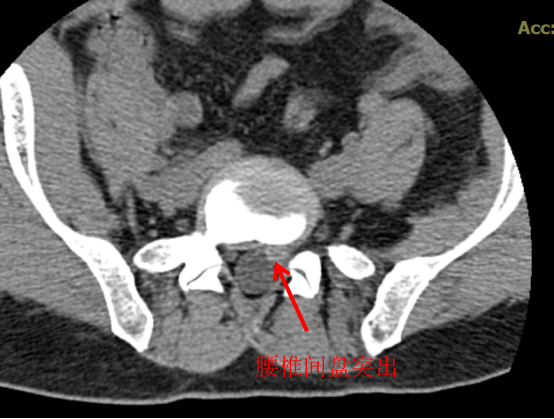

CT 中文名称叫做电子计算机断层扫描,顾名思义就是将需要检查的人体部位,通过电脑切成若干小层,然后把每层的图像显示出来,所以 CT 相对于 X 光片的优点就是细节显示更清楚,一些 X 光片看不出来或看不清的隐匿性骨折,通过 CT 层扫后,就能发现细小的骨折,这样就很大程度上避免了漏诊或误诊。

CT 也可以显示出椎间盘有无突出,椎体内有无骨质破坏、椎管狭窄程度等。所以,如果怀疑一个病人是腰椎间盘突出症,而患者又不愿意做核磁,那就应该首选腰椎 CT。